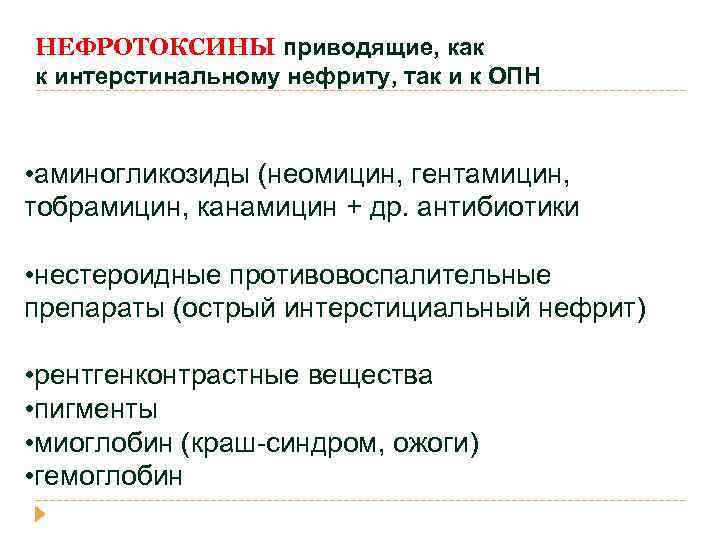

НЕФРОТОКСИНЫ приводящие, как к интерстинальному нефриту, так и к ОПН • аминогликозиды (неомицин, гентамицин, тобрамицин, канамицин + др. антибиотики • нестероидные противовоспалительные препараты (острый интерстициальный нефрит) • рентгенконтрастные вещества • пигменты • миоглобин (краш-синдром, ожоги) • гемоглобин